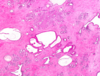

What change to breast tissue is depicted here? [1]

**Microcalcifications** tend to be less common in fibrocystic change than in carcinoma. They tend to be coarse and irregular.